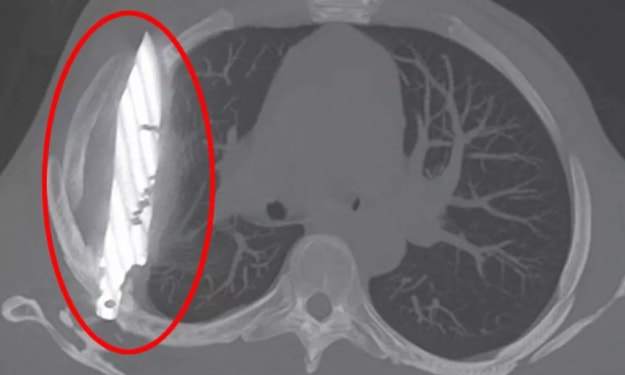

Doctors Discover Large Knife Lodged in Man’s Chest for Eight Years After Hospital Visit for Sore Nipples

When a man in Tanzania visited the hospital to complain about sore nipples and pus discharge, the last thing doctors expected to find was a knife blade lodged in his chest for eight years. The shocking discovery has since made international headlines and has been reported in the Journal of Surgical Case Reports (July 2025).